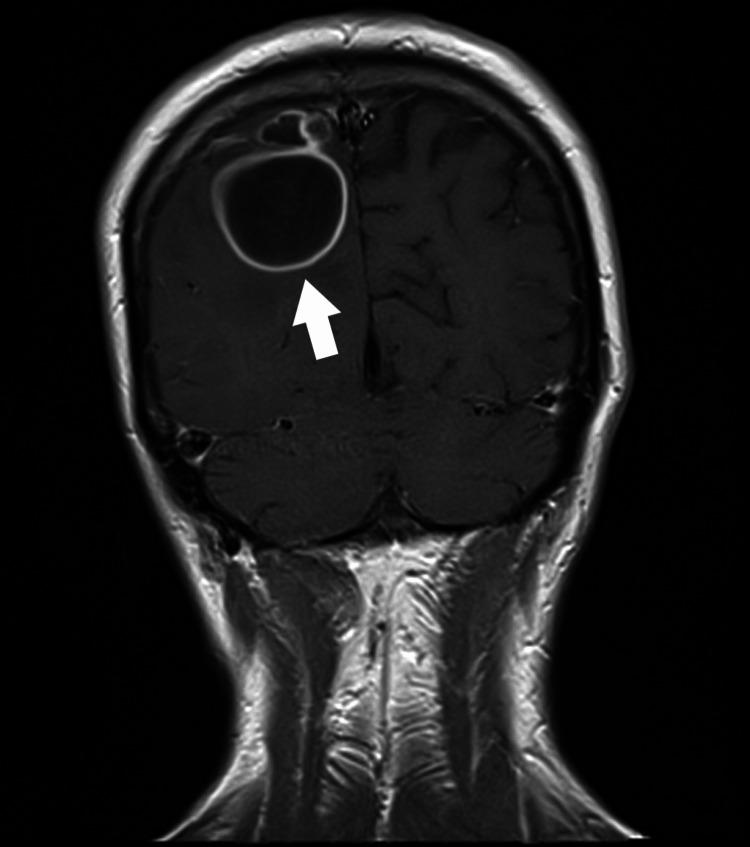

A brain abscess (BA) is a purulent infection of the central nervous system and can be associated with dental procedures. The paper presents a case of a patient diagnosed with an odontogenic BA. On admission, the patient was awake, alert, and oriented (Glasgow Coma Scale 15). The patient reported undergoing excision and drainage of an abscess in the submandibular area three years earlier. An MRI of the head showed a mass lesion (34x19x25 mm) located in the right parieto-occipital region, and an abscess was suspected. During the procedure, puncture and evacuation of the contents of the abscess in the right parieto-occipital area were performed. Oral microorganisms, including and , were isolated from the brain pus. A thorough radiographic and dental examination should be conducted during hospitalization in these patients. Always evaluate for periapical pathology in unexplained BAs, even in the absence of oral symptoms.

脑脓肿(BA)是中枢神经系统的化脓性感染,可能与牙科手术有关。本文介绍了一例被诊断为牙源性脑脓肿的患者。入院时,患者清醒、警觉且定向力正常(格拉斯哥昏迷量表评分为15分)。患者报告三年前曾接受下颌下区脓肿的切除和引流手术。头部MRI显示右顶枕区有一个肿块病变(34×19×25mm),怀疑为脓肿。手术过程中,对右顶枕区脓肿内容物进行了穿刺和引流。从脑脓液中分离出包括[具体微生物名称1]和[具体微生物名称2]在内的口腔微生物。对这些患者住院期间应进行全面的影像学和牙科检查。即使没有口腔症状,对于不明原因的脑脓肿也应始终评估根尖周病变情况。